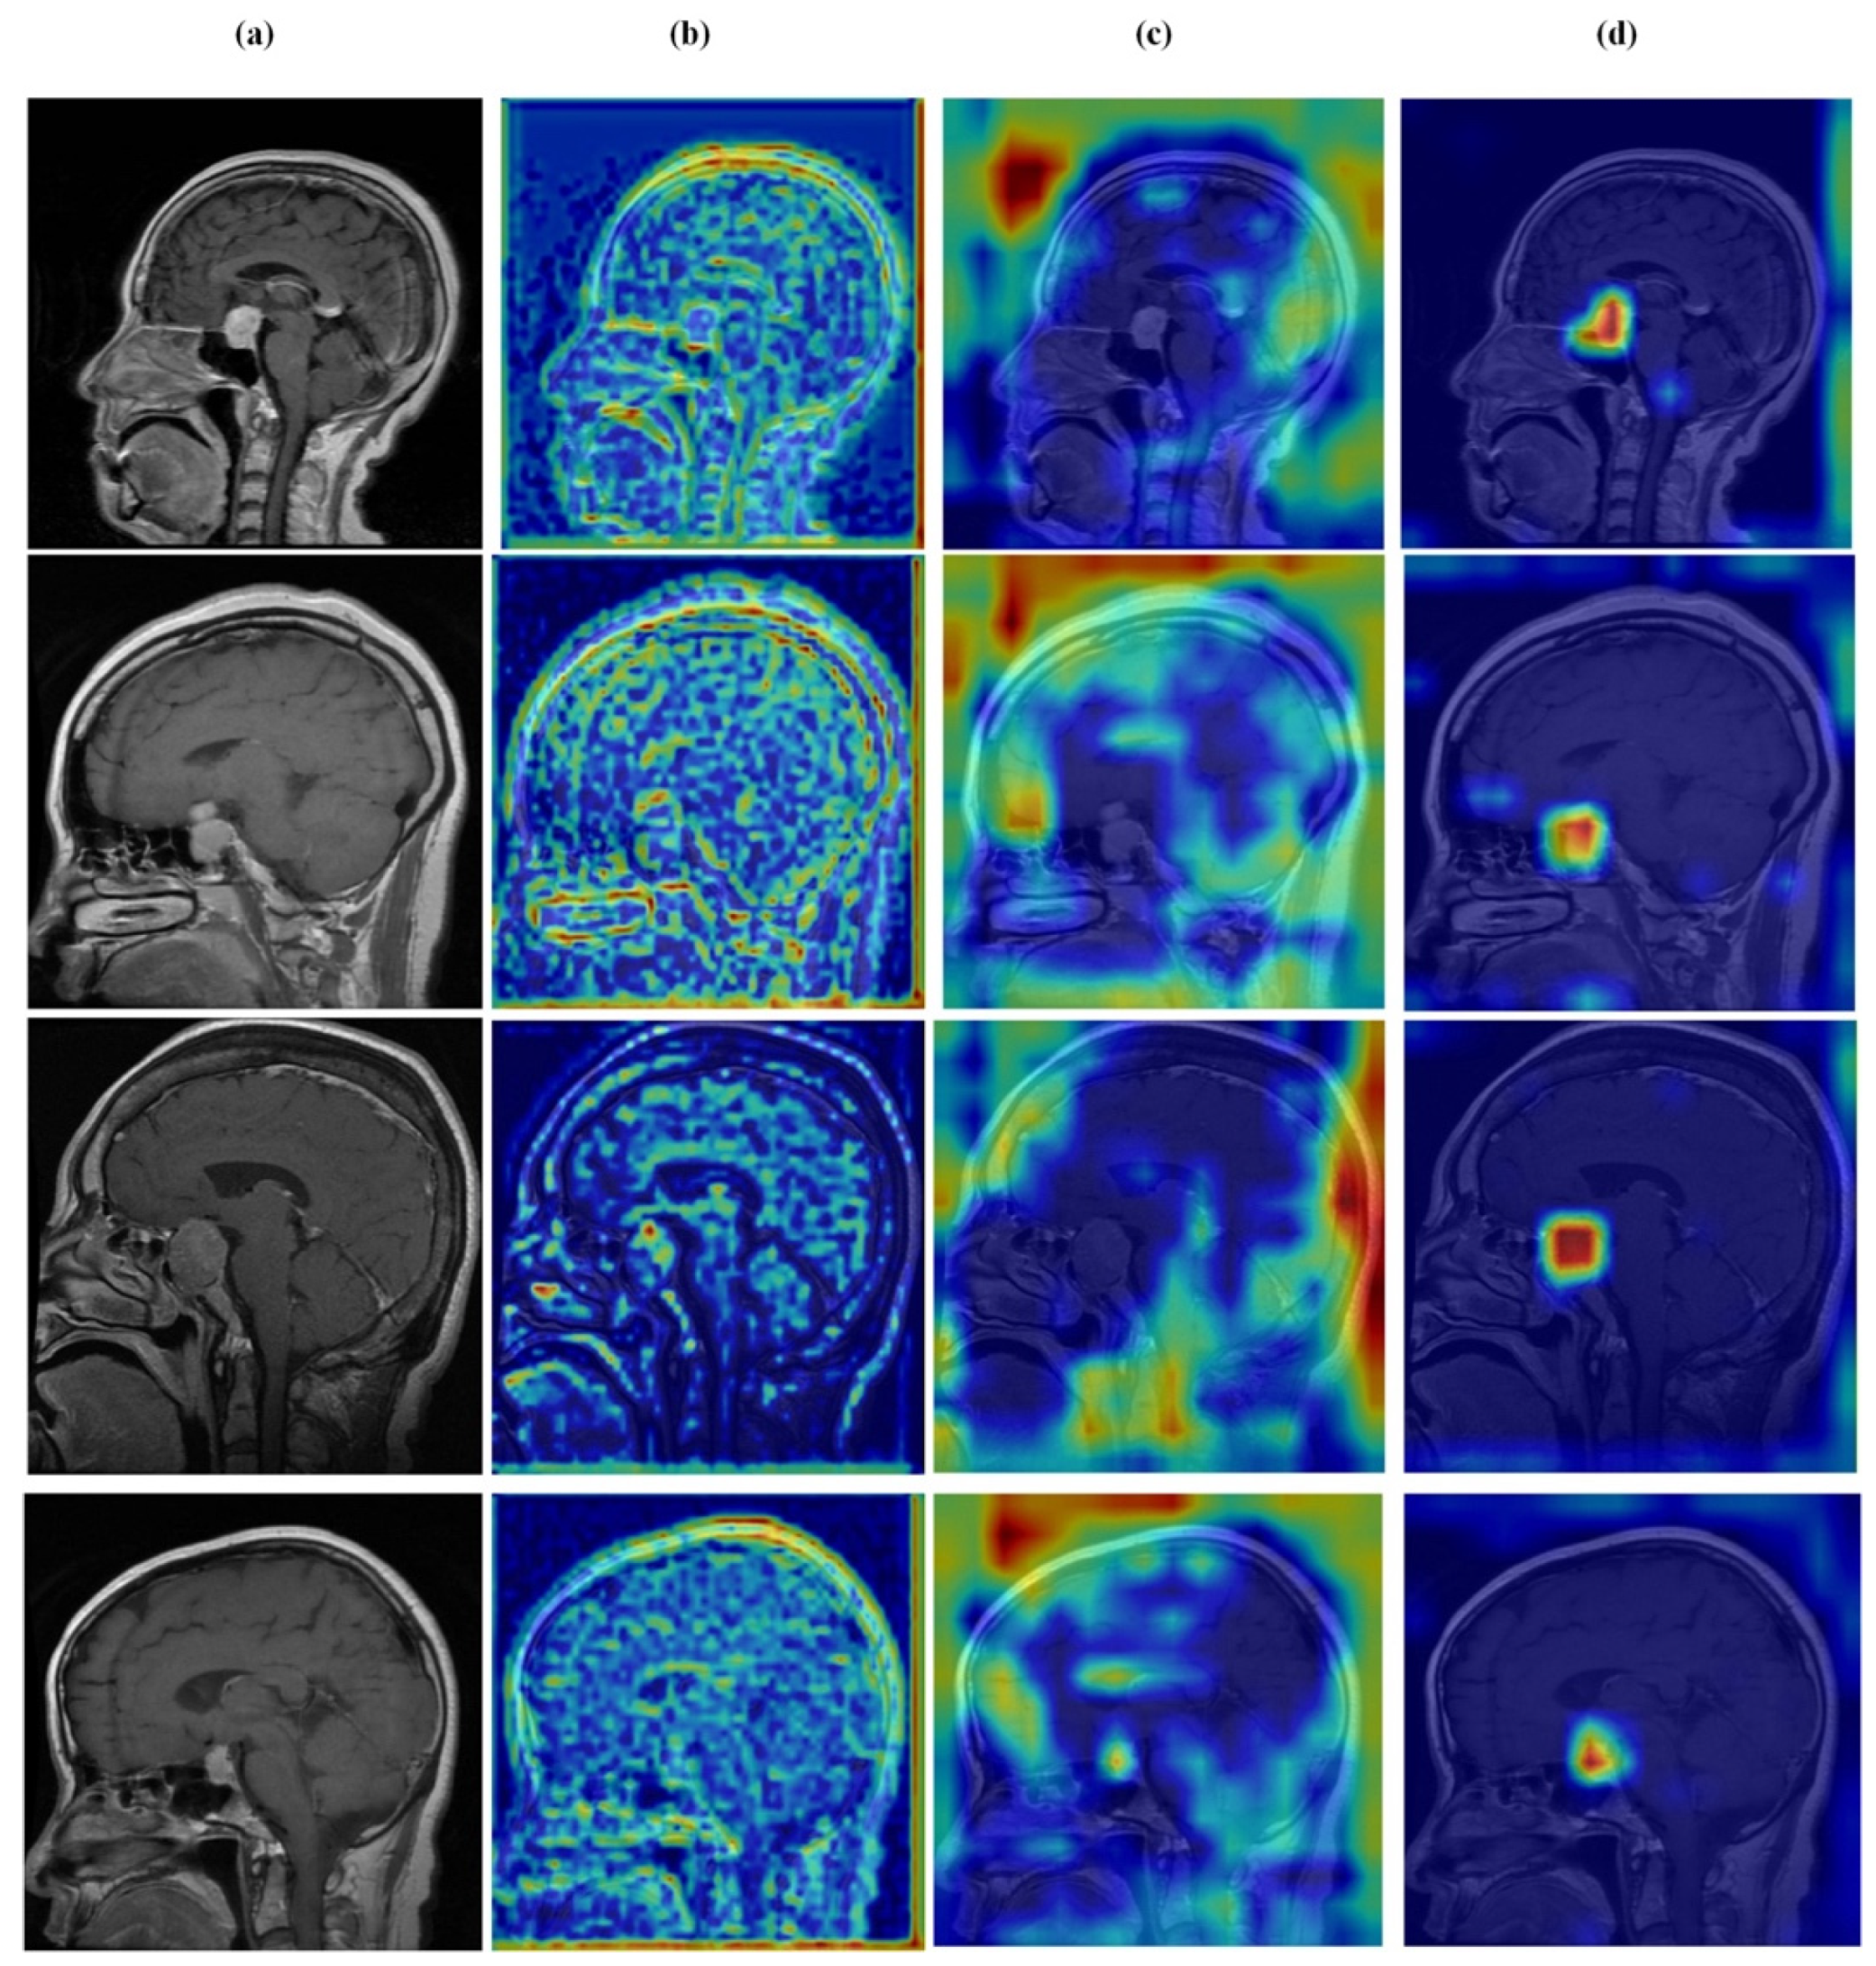

4.7. Feature Learning Analysis

Figure 12, Figure 13, Figure 14 and Figure 15 present Grad-CAM visualizations that trace the hierarchical feature learning of the proposed model across the four classes. Columns are organized as (a) input, (b) high-level features, (c) mid-level features, and (d) low-level features. In (d), the network emphasizes primitive cue edges, intensity transitions, and fine textures capturing sulcal boundaries, skull edges, and generic tissue patterns. Progressing to (c), activations become more structured and context-aware, highlighting coherent anatomical regions and diffuse hyperintense areas that provide spatial context for lesion localization. At (b), class-discriminative focus emerges with responses that contract tumor-centric hotspots for glioma and meningioma and to the sellar region for pituitary cases, while no_tumor images exhibit suppressed high-level responses, reflecting the model’s rejection of false lesion cues. This bottom-to-top progression from generic edges to task-specific evidence explains the model’s improved decision reliability and aligns with the multi-task design that encourages precise, clinically meaningful attention.

Figure 13.

Visual representation of feature activations in glioma tumor cases. (a) input, (b) low-level features, (c) mid-level features, and (d) high-level features.